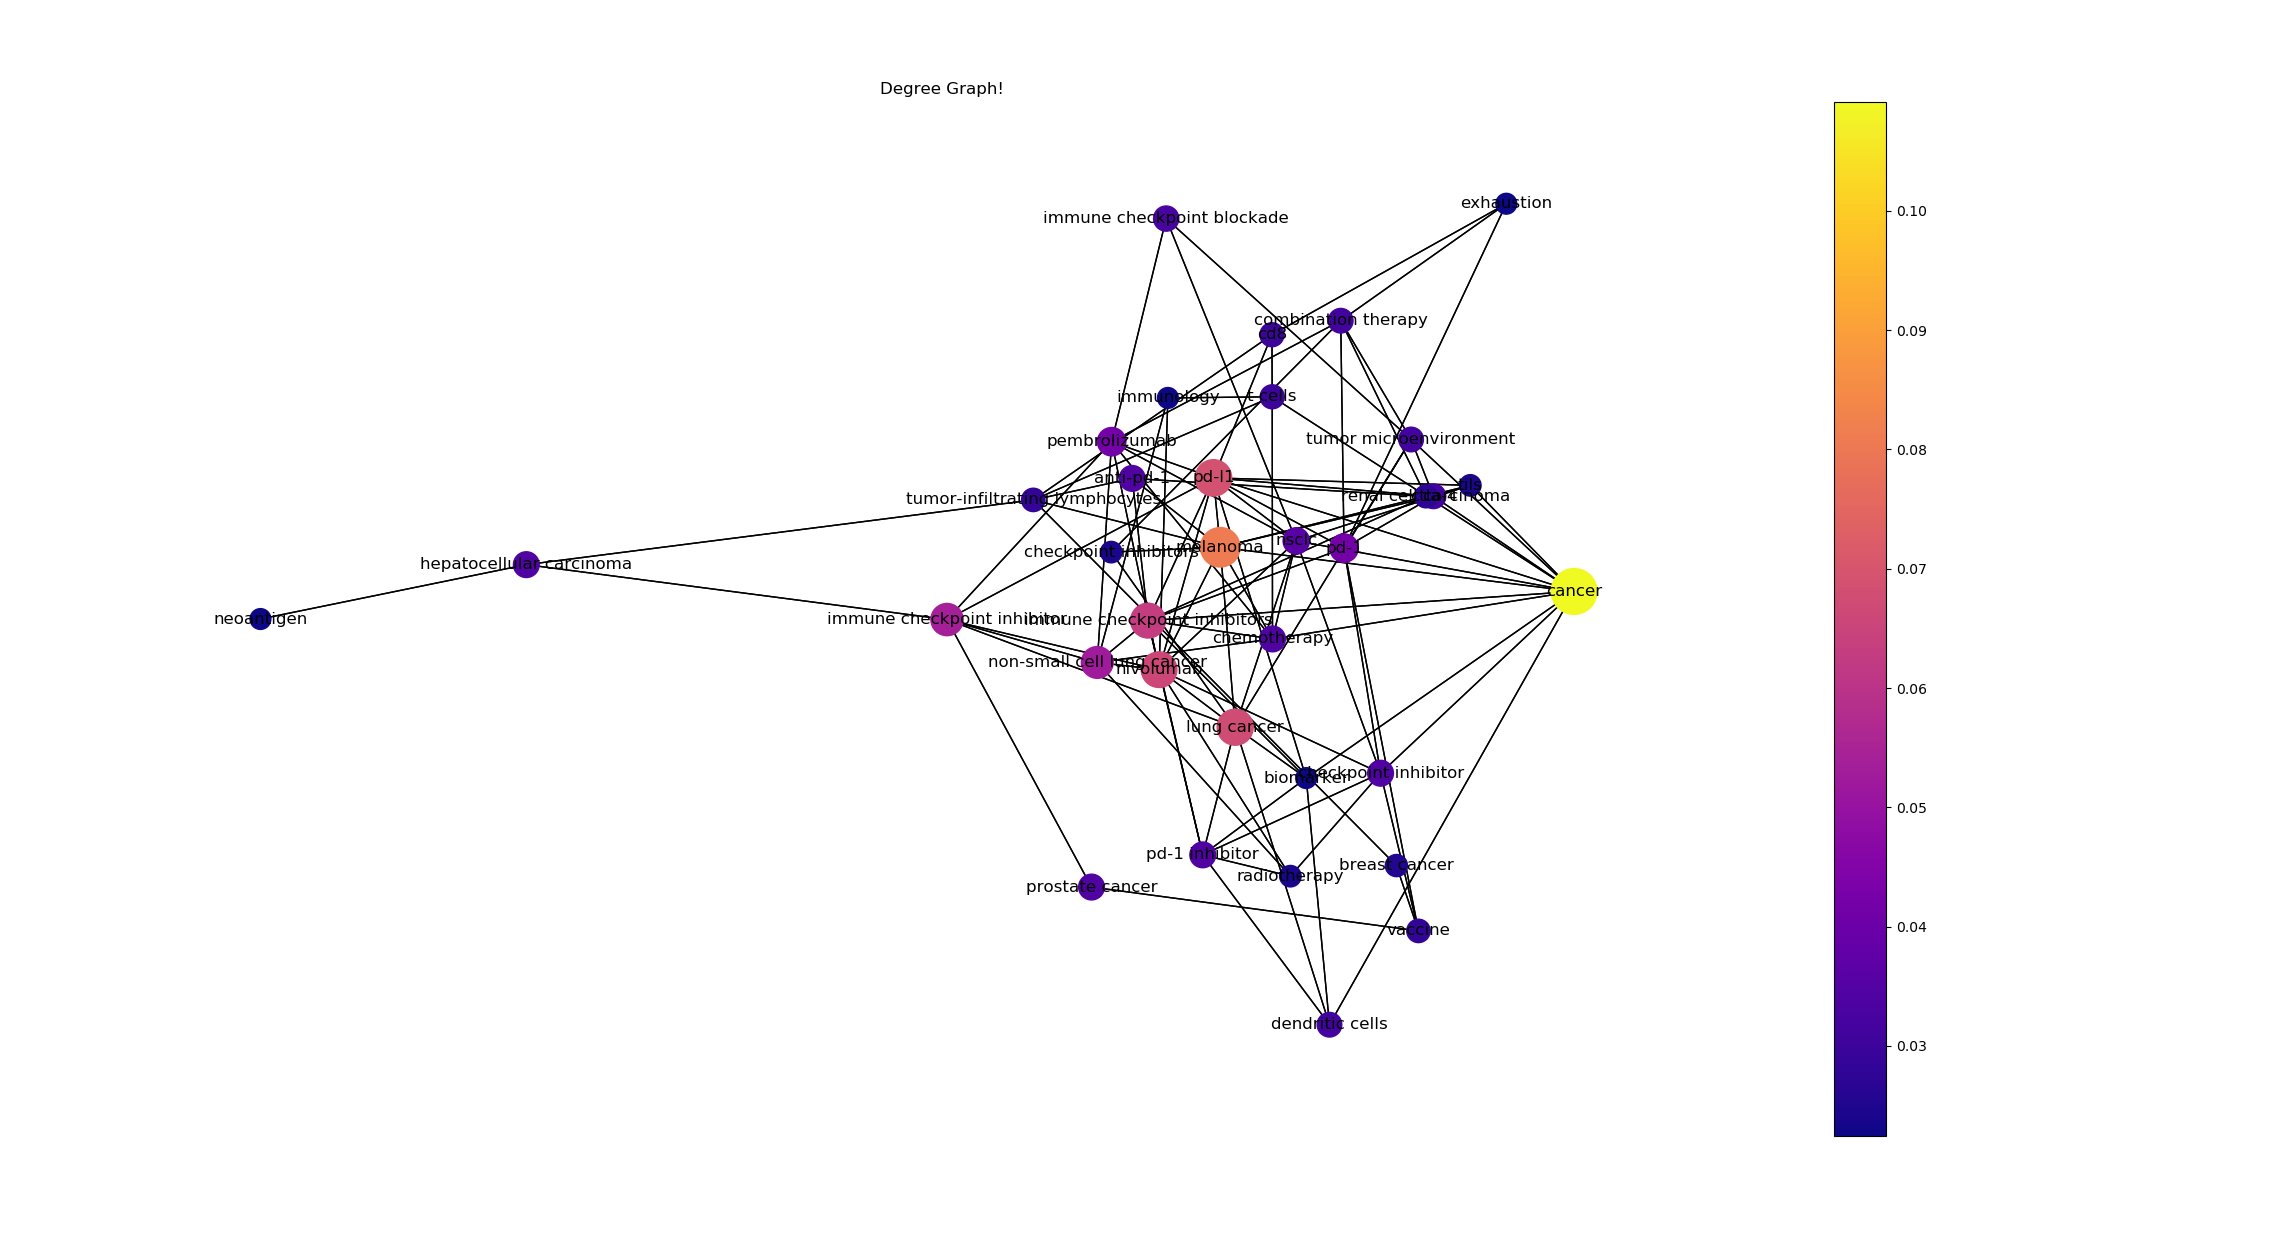

결과

- 데이터 셋에서 100개의 논문 중 상위 5프로의 키워드를 기반으로 도출된 DC(Degree_centrality) 그래프